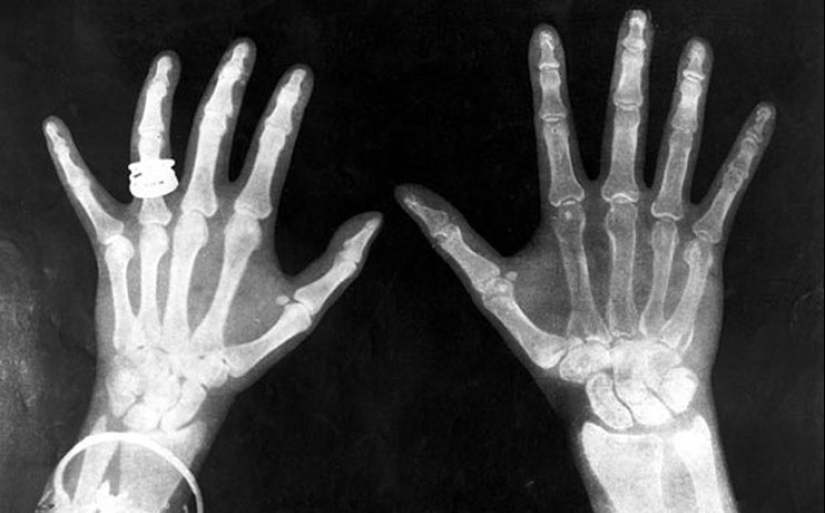

Los rayos X

Todo el mundo al menos una vez en la vida la puso para el diagnóstico a través de la máquina de rayos x. El descubrimiento de los rayos x fue un gran avance en la medicina y en otros campos. Cosmetología también trató de utilizar la invención. X-ray fue considerado como un medio confiable para la eliminación del vello. Después de un par de sesiones el vello no deseado de caerse. Al mismo tiempo, creció de edad, creció la piel delgada. La mayoría de las terribles consecuencias que tuvo lugar en un par de años. La depilación con la ayuda de la máquina de rayos x condujo a un aumento en la incidencia de cáncer de piel.